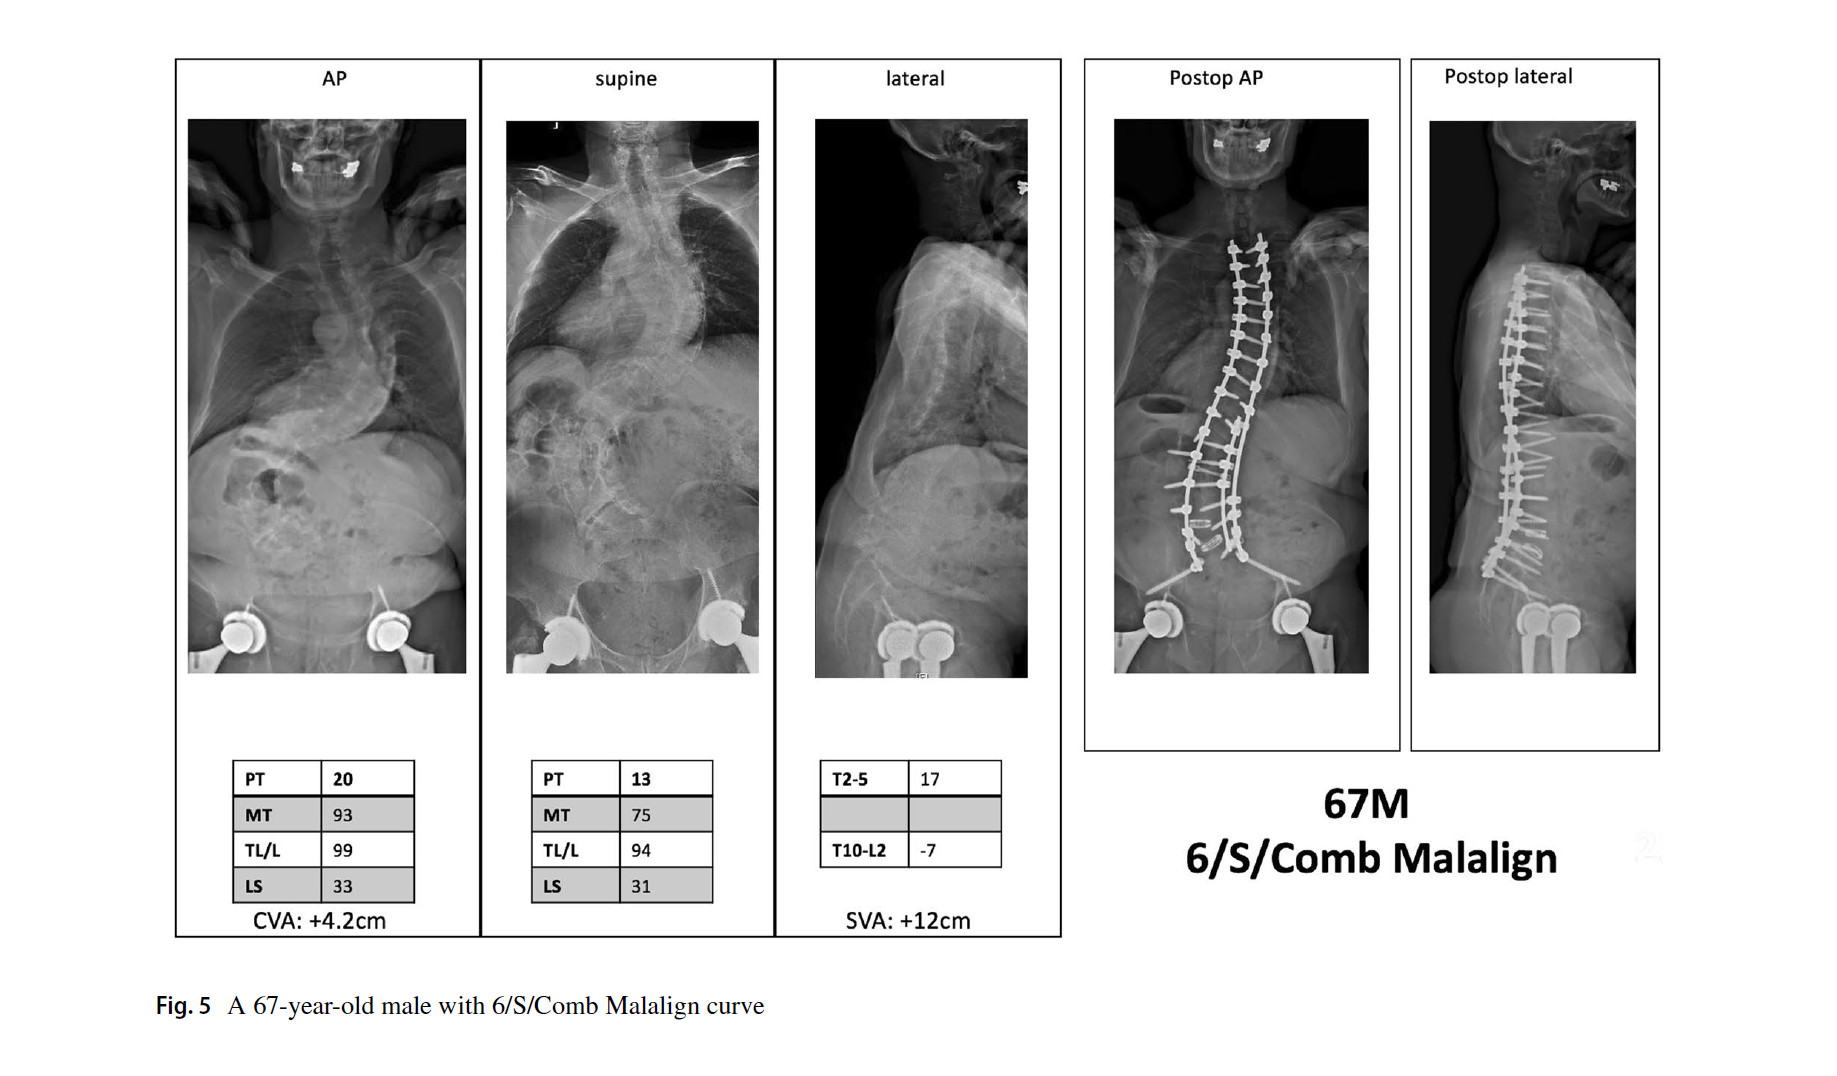

3. 脊柱平衡修正包括了冠状位、矢状位和冠矢合并的平衡状态。标准与SRS基本一致,冠状位失衡CVA≥40mm,矢状位失衡SVA≥40mm。排列组合,共有Aligned、Sag Malalign、Cor Malalign、or Comb Malalign 4种类型。如果脊柱失衡,需要按SRS标准矫正。

文中的病例片子很漂亮,看图知意,很容易让读者理解这个分型。